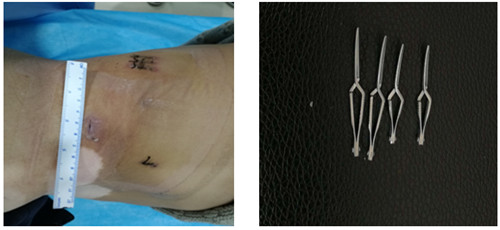

如圖一圖二為腫瘤位置及大小,圖三即為手術(shù)操作通道(5mm、10mm、12mm),術(shù)中游離出腎動(dòng)脈后,用圖四的血管夾臨時(shí)阻斷腎臟血液供應(yīng),剜除腫瘤后,在腔鏡下縫合腎臟,確定縫合嚴(yán)密,再恢復(fù)腎臟血供!要求阻斷時(shí)間不能超過(guò)30分鐘,此例患者阻斷17分鐘!此類手術(shù)技術(shù)難度大,腹腔鏡下縫合要求高,并對(duì)血供阻斷有時(shí)間要求!